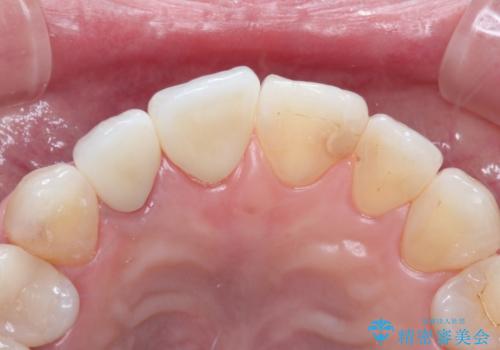

前歯が痛い。根管治療~オールセラミッククラウン

根管治療を行った後、オールセラミッククラウン(エクセレント)にて治療を行いました。

被せものの色調を合わせるためには数回の修正が必要になることがあります。